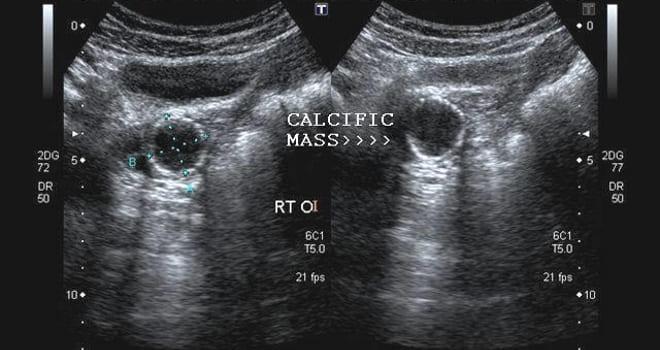

Кальцинат яичника, будь то правый или левый, представляет собой образование, образованное отложениями кальциевых солей. Для точного определения его природы необходима квалифицированная диагностика.

Кальцинаты в яичниках, выявленные при ультразвуковом исследовании, вызывают интерес и порой беспокойство как у пациентов, так и у врачей. Эксперты отмечают, что наличие кальцинатов может свидетельствовать о различных процессах в организме. В большинстве случаев это не является признаком серьезного заболевания, а может быть результатом старения тканей или предшествующих воспалительных процессов. Однако важно учитывать, что кальцинаты могут также указывать на наличие опухолей, как доброкачественных, так и злокачественных. Поэтому специалисты рекомендуют проводить дополнительные исследования для уточнения диагноза. Важно, чтобы пациент не паниковал, а обсудил результаты УЗИ с врачом, который сможет дать рекомендации по дальнейшим действиям и необходимым обследованиям.

- Ультразвуковое исследование (УЗИ) позволяет обнаружить кальцинаты в яичниках. Существует три метода проведения УЗИ, из которых трансвагинальный считается наиболее информативным, так как введение датчика во влагалище дает возможность получить детальную информацию о состоянии половых органов;